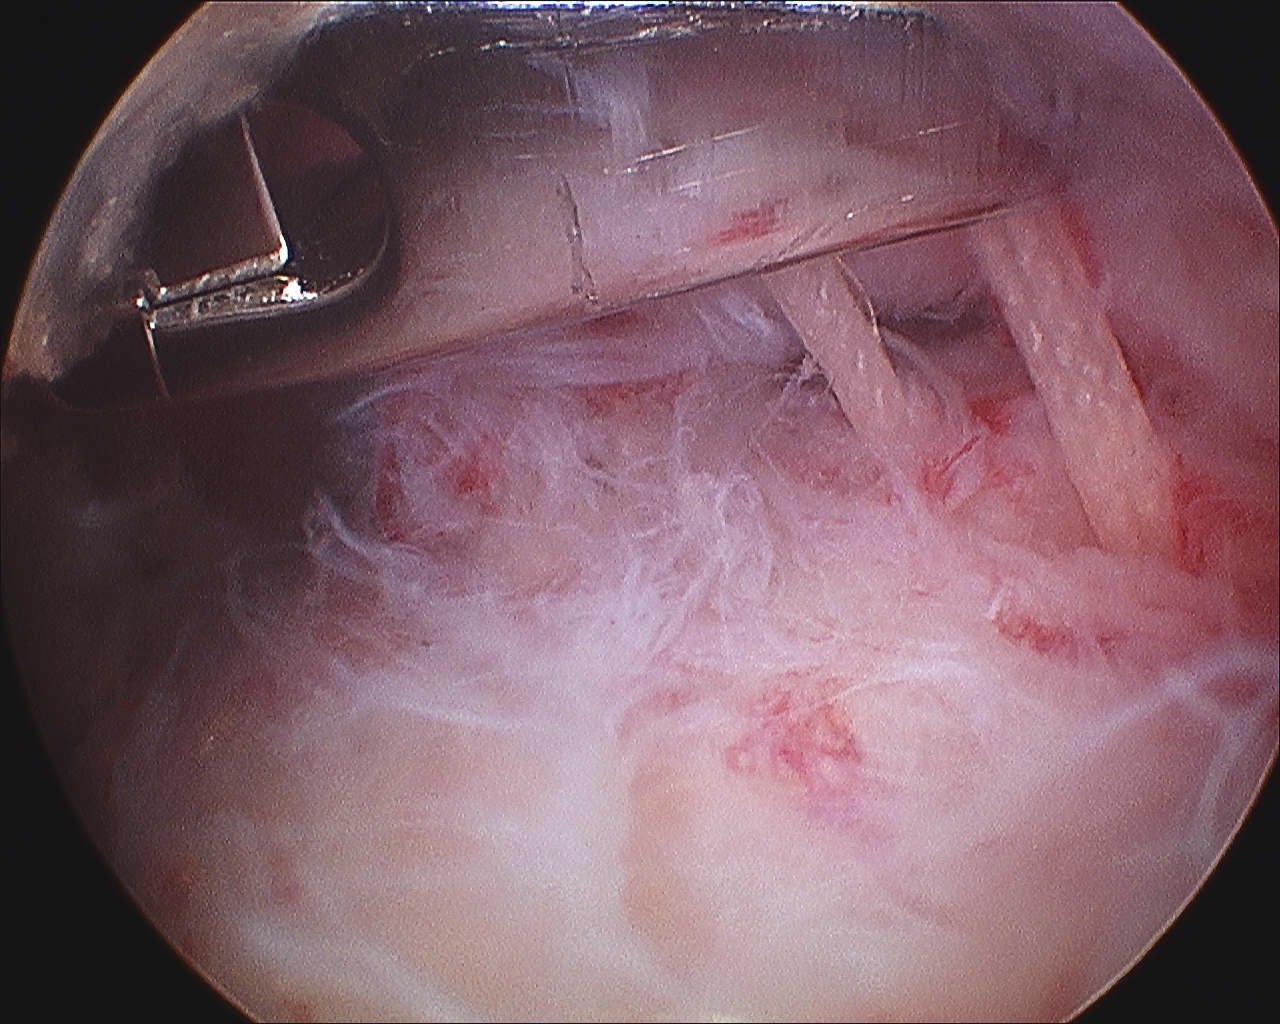

Articular side

Normal insertion of undersurface of the rotator cuff onto the footprint, with camera in glenohumeral joint